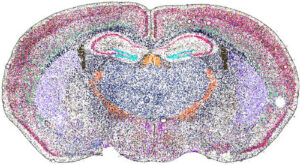

Spatial biology is a rapidly advancing discipline that examines biological molecules (such as DNA, RNA, and proteins) within their native locations in tissues. This approach offers critical insight into how cancer and immune cells interact within the tumor microenvironment.

Beginning in the 20th century, techniques such as immunohistochemistry and in situ hybridization allowed researchers to localize proteins and nucleic acid sequences directly in tissue samples. However, these analyses were typically limited to a single marker at a time. More recently, advances in high-throughput sequencing and mass spectrometry enable the simultaneous analysis of hundreds, or even thousands, of molecules while preserving spatial context. To explore the future of spatial biology, we spoke with four companies pioneering these technologies.

The transcriptome is the complete collection of RNA produced in a cell or tissue at a given time. It reflects active gene expression, which varies with disease state and environmental conditions. Understanding the transcriptome is therefore crucial for studying cancer biology and treatment response.

Pratheesh Sathyan, PhD, head of AMR oncology at Illumina, says that the company plans to roll out a new spatial transcriptomics platform for commercial release in 2026. He describes several advantages of spatial transcriptomics.

“Immune cells are an important part of our defense against cancer. And spatial approaches help to understand how immune cells interact with the tumor,” he says. “With spatial transcriptomics, you are maintaining the true habitat of the tissue, and that helps us with better diagnostics and better precision therapy.”

Since then, a great deal of progress has been made in the field. Segale notes that Illumina’s platform will enable sampling of more than seven square centimeters of tissue. “This allows you to look at large bits of tumor microenvironments. More than other products available today,” he says.

Another key feature of the upcoming product is whole transcriptome coverage. “Many spatial transcriptomics platforms look at panels of typically 5,000 unique transcripts,” notes Segale. “In contrast, we are seeing 30,000 to 40,000 unique RNA transcripts per sample. It is completely unbiased and hypothesis-free. There is a real richness of information that we are seeing.” Finally, the platform will enable 1-micron spatial resolution, allowing researchers to see key surface features on the cellular level.

“The information from our new platform will allow us to differentiate different cell types from one another and even identify new markers and new subtypes,” says Segale. “This is important because much of the cellular structure of the human body still has not been mapped, including organs and various tissues.”

Easterling recounts a collaboration with Stanford University and the Medical University of South Carolina to spatially localize glycans in different tissues. This information was then combined with spatial transcriptomics and proteomics layers to analyze gliomas, a lethal cancer with very limited treatment options. Ultimately, the glycomics information emerged as the strongest classifier of tumor grade across all three omics layers.